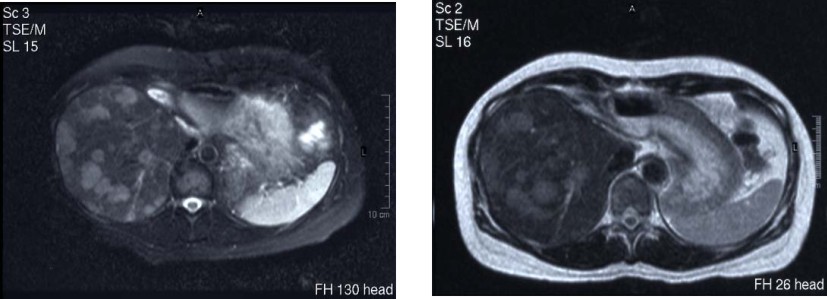

病例5 结肠癌

A 治疗前DSA B 灌注CMI化疗药物立即造影瘤染色明显减少

C 治疗前MRI见乙状结肠病灶 D 治疗后病灶缩小